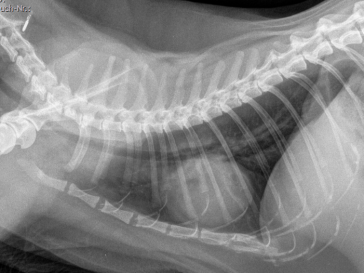

Eine Vergrösserung der Herz-Silhouette auf beiden Aufnahme-Ebenen des Brustkorbes – aber auch eine Verdichtung des Lungengewebes (Flüssigkeitsansammlung im Interstitium den Bronchien und Alveolen) sind ernste Zeichen und veranlassen entweder direkt einen Therapieversuch, oder führen zu den unten aufgeführten weiteren Untersuchungen.

Röntgenaufnahmen des Brustkorbes auf zwei Ebenen mit vergrössertem und abgerundetem Herzschatten und Verdichtung im Lungengewebe.

Thorax Röntgen

seitliches Thorax Röntgen mit vergrösserter Herz-Silhouette und verdichtetem Lungengewebe